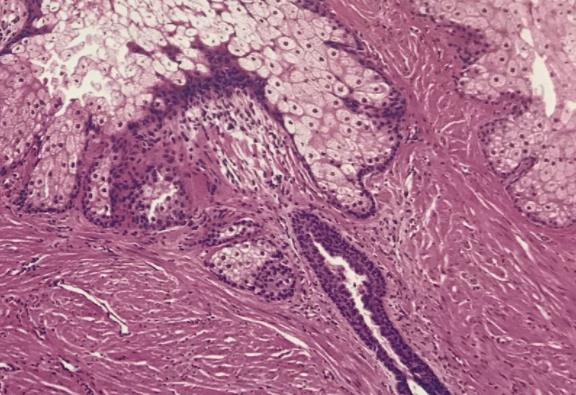

乳晕变黑,乳晕周围的皮脂腺增生,形成分散的结节状小隆起,称为蒙氏结节。怀孕期间,胎盘分泌大量雌激素刺激乳腺发育,并分泌大量孕酮刺激乳腺发育。垂体催乳素、胎盘催乳素、胰岛素、皮质醇和甲状腺激素也参与乳腺的发育。